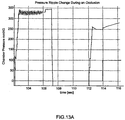

- Fig. 1 is a schematic representation of a hemodialysis system.

- the present invention generally relates to hemodialysis and similar extracorporeal blood treatment systems.

- the various systems and methods described herein are described in relation to hemodialysis, it should be understood that the various systems and method described herein are applicable to other dialysis systems and/or in any extracorporeal system able to treat blood or other bodily fluids, such as hemofiltration, hemodiafiltration, etc.